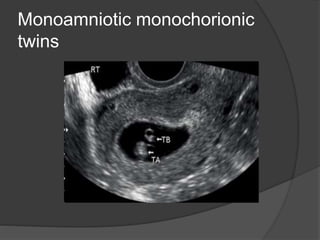

Monoamniotic monochorionic

twins

Multiple Pregnancy  Multiplepregnancies and types of twinning depends on the number of zygotes and timing of division and they are : 1- Dizygotic twins : two fertilized ova and they are all dichorionic , diamniotic 2- Monozygotic twins : the amnionicity and chorionicity depends by the time of zygote division - Before 3rd day post conception : diamniotic, dichorionic - 4th-8th day post conception : monochorionic , diamniotic - Cleavage of the inner cell mass of blastocyst after 8th day post conception : monochorionic, monoamniotic. - Incomplete cleavage of embryonic disc after 13th day post conception : conjoined twins